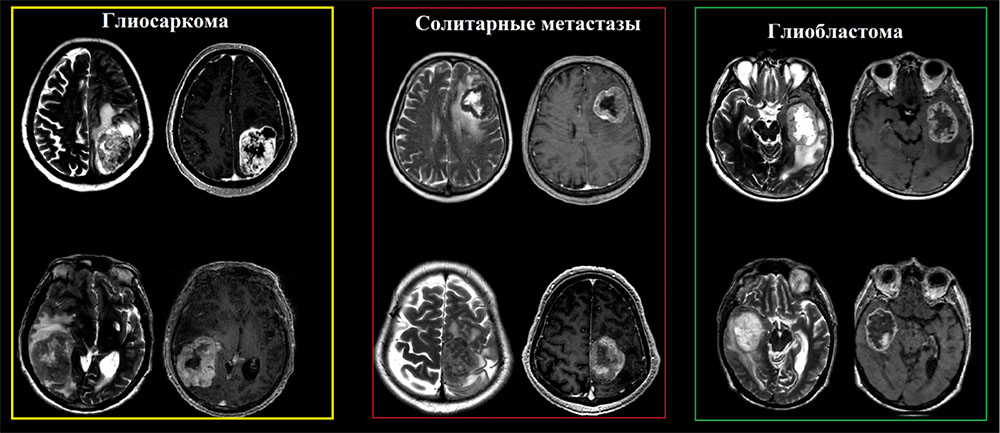

Частота встречаемости глиосарком составляет от 1% до 8% от всех злокачественных глиом, пик встречаемости 4-6 декады жизни с преобладанием мужской популяции, с медианой выживаемости около 9 месяцев. Глиосаркомы имеют общие и практически не отличимые визуализационные характеристики в сравнении с классическими глиобластомами и в большинстве случаев диагноз устанавливается после иммуногистохимического исследования. Стоит отметить, что глиосаркома обладает более высокой тенденцией к экстракраниальному метастазированию (наблюдаются в 30% случаев), последние включают висцеральные органы и спинной мозг.

Глиосаркома должна быть включена в дифференциальный ряд любой опухоли, которая, по-видимому, является интрааксиальной, но при этом «интимно» прилежит к твердой мозговой оболочки и демонстрирует гетерогенные визуализационные характеристики на T2-взвешенных изображениях.